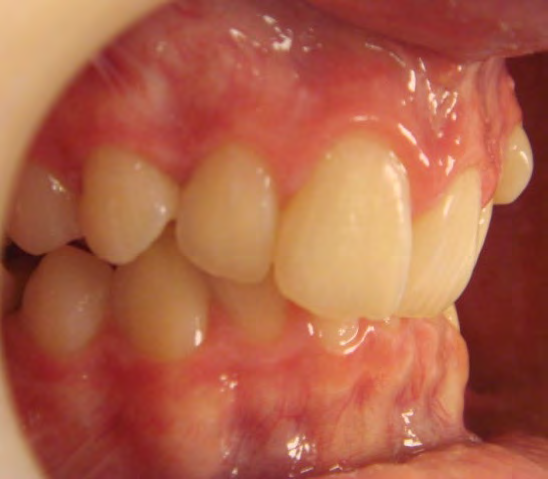

Below are cases treated at Vakresmil without extractions within the last three years. The families had been told, “It is simply not possible for your child to be treated without extractions” by orthodontists. Judge for yourself if that was right or wrong.

The overall aim is to produce the best smile we can — a “beautiful smile”, if you will — without premolar extractions, headgear, facemasks or banded appliances. A smile that both the patient and we at Vakresmil can be proud of.